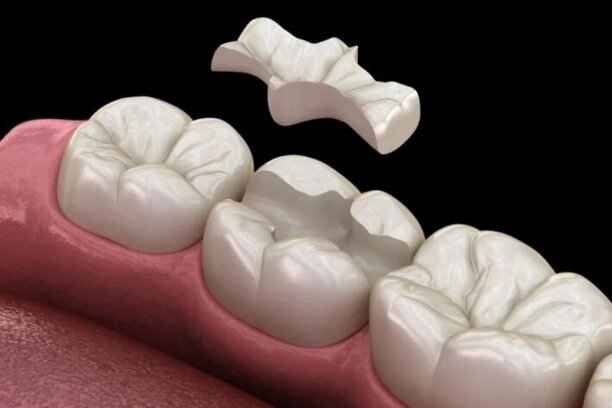

3. حشو السيراميك

خيار متقدم يجمع بين الجمال والمتانة، ويُستخدم غالبًا في الحالات التي تتطلب مظهرًا راقيًا وعمرًا أطول. يمتاز حشو السيراميك بـ:

- مقاومة عالية للتصبغات وتغير اللون.

- مظهر قريب جدًا من الأسنان الطبيعية.

- تحمل جيد لقوى المضغ.

- سطح أملس يقلل من تراكم البلاك.

- ملاءمة ممتازة للحالات التجميلية المتقدمة.

- مواد خزفية أو سيراميكية مقاومة للتآكل وثابتة اللون.

- الحشوات السيراميكية: مظهر جمالي ممتاز، مقاومة للتصبغات والتآكل، وتدوم طويلًا.

- الحشوات السيراميكية: صلبة وجمالية، مقاومة للتصبغ وسهلة التنظيف.

- الحشوات السيراميكية: تدوم من 10 إلى 15 سنة، خاصة للأسنان الأمامية مع تجنب الصدمات.